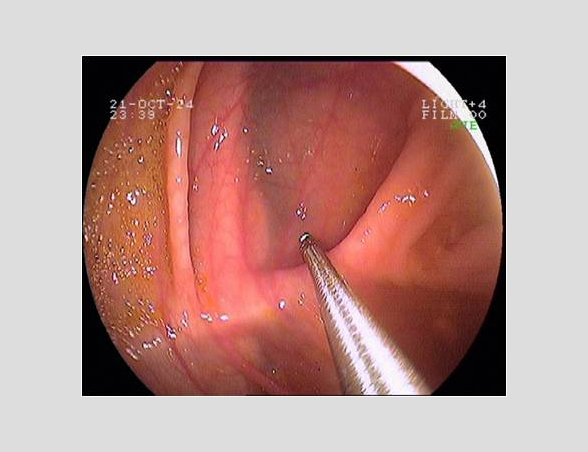

Imágenes tomadas durante la endoscopia digestiva alta y la colonoscopia. Se aprecia una mucosa de aspecto y vascularización normal, sin lesiones visibles. Se progresa con el colonoscopio hasta el íleon. Todo resulta macroscópicamente normal. Se toman biopsias de todos los segmentos explorados.

La endoscopia es el método de elección para el diagnóstico y seguimiento de la EII. Permite una visión macroscópica de la mucosa intestinal y la toma de múltiples biopsias para el estudio histológico.

Realizamos una endoscopia digestiva alta y una colonoscopia a la paciente con toma de biopsias, obteniendo el informe de Anatomía patológica.